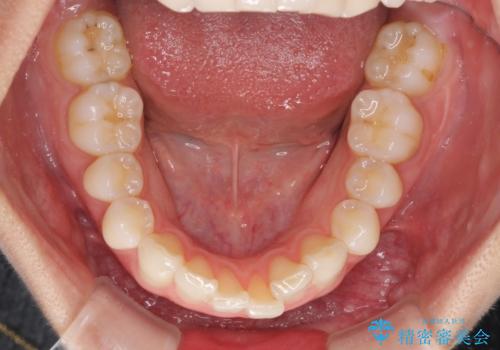

- 上下前歯の叢生を気にして来院された患者様です。

以前矯正をした後戻りということで、歯列不正はそれほど大きくなかったため、インビザライン・ライトを用いて矯正治療を行うこととしました。

前歯のデコボコが残っており、シミュレーション通りに動いていない部分がありましたが、再矯正であることやご本人の満足いくところまでデコボコが改善されたとのことで、治療を終了することとしました。